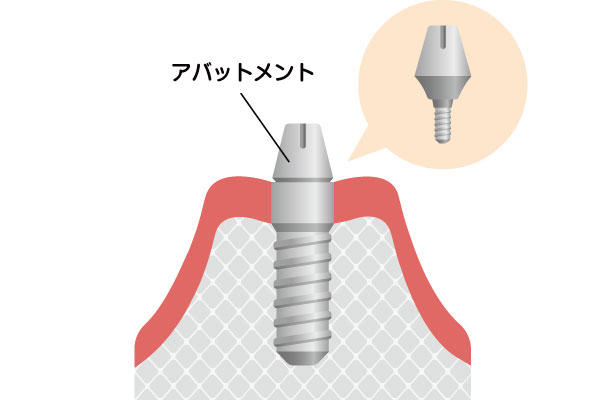

二次手術

アバットメント(土台)の接続

二次手術

インプラントが骨としっかり結合したことを確認後、歯ぐきをわずかに切開して、被せ物の土台となる「アバットメント」を装着します。

※骨の状態や術式によっては、一次手術と同時に行う場合もあります。